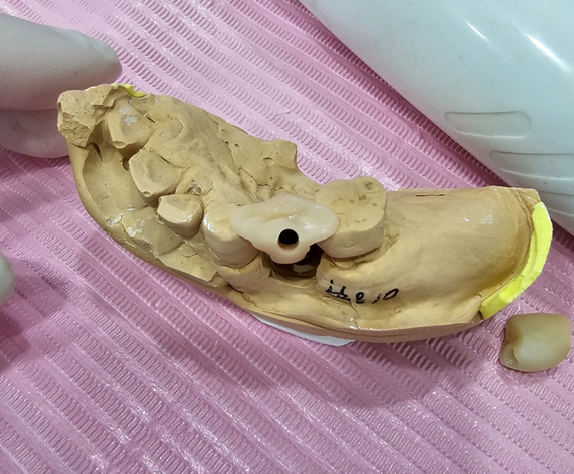

거기다 실제 임프레션도 해볼 수 있도록

러버와 임플란트 모델까지 준비해서

마음껏 연습할 수 있도록 했답니다!

아래는 실제 학생들이 인상채득한 거에요!

잘했쥬?

76-1인상채득종류24min

임프레션에 따른 코핑종류와 재료 인상채득에 대해 알수있다

86-2임프레션후스톤13min

임프레션부터 그후에 모델이 어떻게 제작이 되는지 방법등과 임프레션에 대해 영상을 통해 알아본다